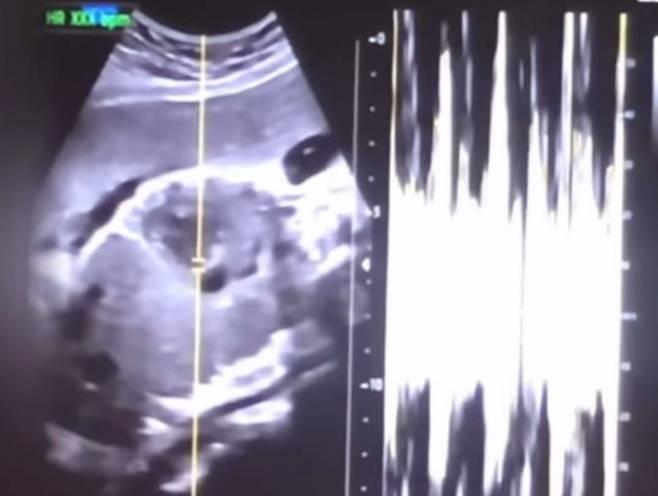

검찰이 임신 36주차 산모를 대상으로 제왕절개 수술을 한 병원장에게 징역 10년을 구형했다.

검찰이 임신 36주차 산모를 대상으로 제왕절개 수술을 한 병원장에게 징역 10년을 구형했다. 산모에게도 살인 혐의를 적용해 징역 6년을 선고해달라고 재판부에 요청했다.